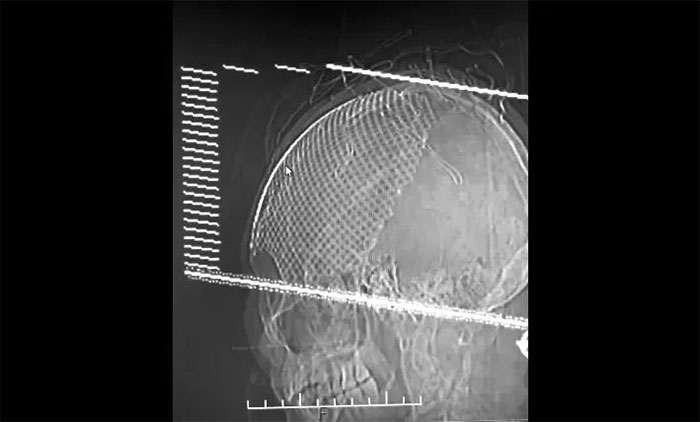

▲ 修补后的完整颅骨图像

王女士虽恢复良好,但颅骨缺损较为严重(13cm*13cm),已影响到了正常生活。经评估,手术指征明显,无手术禁忌。在征得家属同意的情况后,于耀宇主任团队为她进行了颅骨钛板修补手术。手术过程顺利,术后安返监护病房。